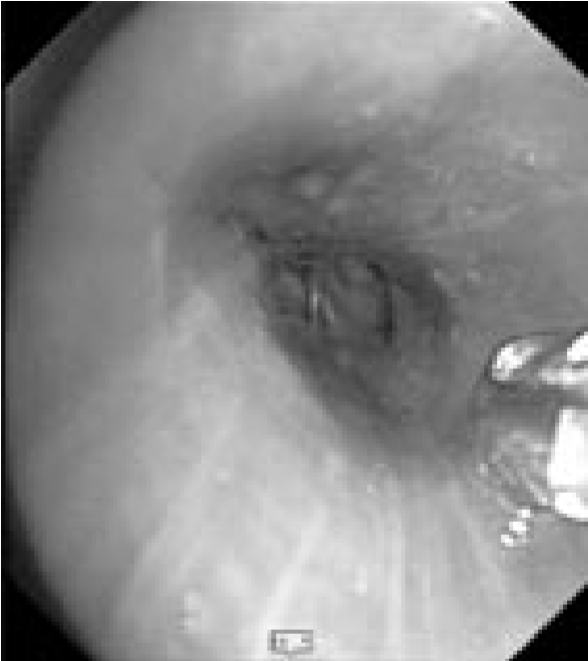

В связи с сочетанным характером патологии (поражение как легочной ткани, так и средостения) было запланировано проведение комбинированного двухэтапного эндоскопического исследования. На первом этапе предполагалось выполнить видеобронхоскопию в стандартном разрешении с детальным осмотром верхнезонального бронха левого легкого, бронхоальвеолярный лаваж (БАЛ), при наличии технической возможности – браш-биопсию и щипцовую трансбронхиальную биопсию легкого. На втором этапе планировалось провести эндоскопическую ультрасонографию средостения эхобронхоскопом (ЭУС-б) с визуализацией бифуркационного лимфоузла с последующей тонкоигольной пункцией. Все исследования планировалось осуществить в условиях местной анестезии. 23.08.2017 г. пациенту выполнена видеобронхоскопия бронхоскопом Olympus BF 1Т150 (Olympus Corp., Japan). Интубация проведена через правый носовой ход. По результатам исследования гортань без особенностей. Трахея свободна, отделяемого нет. Бифуркация не расширена, карина острая, подвижная, устья бронхов 1–5-го порядка справа открыты, не деформированы, в просвете сегментарных бронхов единичные комочки слизистой мокроты. Слизистая видимых бронхов справа несколько отечна, гиперемирована. Слева: при осмотре бронхов верхней доли определяется перибронхиальный стеноз устья LВ1-2 до 3 степени, признаков пролиферативного поражения слизистой в указанной зоне нет. При акваскопии – устье стенозированного бронха открывается, признаков специфического поражения слизистой не выявлено. Слизистая бронхов слева умеренно гиперемирована, отечна (рис. 2).2

Рис. 2. Видеобронхоскопия пациента А., эндофото:

а – шпора верхнедолевого бронха левого легкого, визуализируется просвет нижнедолевого бронха (на 6 часов), на 12 часов – устья язычковых бронхов и верхнезонального бронха левого легкого; б – устье верхнезонального бронха левого легкого (LB1-2 и LB3), четко визуализируется продольный характер складчатости слизистой; в – детальный осмотр ветвей верхнезонального бронха: визуализируется перибронхиальное сужение устья LB1-2 до практически полного исчезновения просвета, дистальные ветви данного бронха осмотру недоступны, устье LB3 без особенностей, отмечается точечная пигментация слизистой над устьем LB1-2; г – осмотр устья бронха LB1-2 с помощью акваскопии (введение лаважного раствора в устье бронха под давлением) – признаков опухолевого либо специфического (туберкулезного) поражения слизистой не выявлено; д – осмотр устья бронха LB1-2 после выполнения акваскопии и забора БАЛ – скудное поступление пенистого отделяемого (по сравнению с активным дренажом из устья LB3 – на 4 часа); е – попытка выполнения щипцовой трансбронхиальной биопсии через устье LB1-2 (визуализируются бранши биопсийных щипцов – на 4 часа).

Пациенту выполнен комплекс биопсий в объеме: БАЛ через LВ1-2 (крайне скудный возврат), браш-биопсия там же. Проведение щипцовой биопсии в указанной зоне оказалось технически невозможным (высокий уровень отхождения бронха). Полученный диагностический материал был направлен на цитологическое и микробиологическое исследования (люминесцентная микроскопия, молекулярно-генетическое исследование, посев на жидкие питательные среды на МБТ) для верификации диагноза. Эндоскопическое заключение: Стеноз устья LВ1-2 до 3 степени, перибронхиальная форма. Диффузный двусторонний неспецифический бронхит 2 степени2